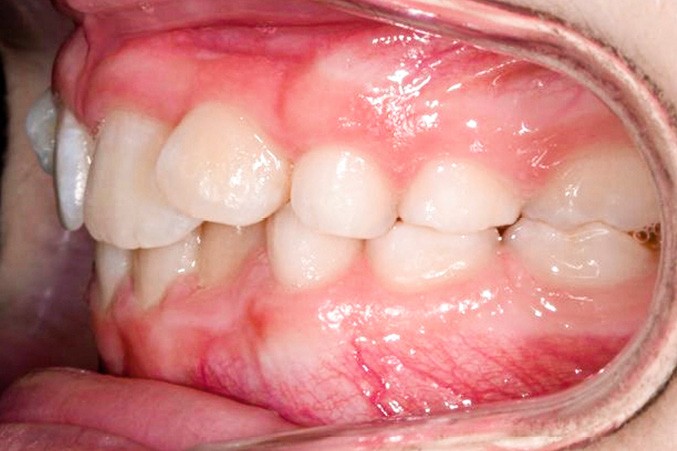

La patiente consulte à l’âge de 9 ans pour la malposition de ses incisives latérales maxillaires. Elle présente une occlusion de Classe I bilatérale sur un schéma normodivergent avec une dysharmonie dento-maxillaire en denture mixte. À l’arcade maxillaire, elle présente une endoalvéolie avec rotations mésiopalatines de 16 et 26.

Le traitement vise à mettre en place les canines maxillaires en Classe I sans porter atteinte à l’intégrité des incisives, tout en conservant l’occlusion de Classe I molaire et en corrigeant la dysharmonie dento-maxillaire.